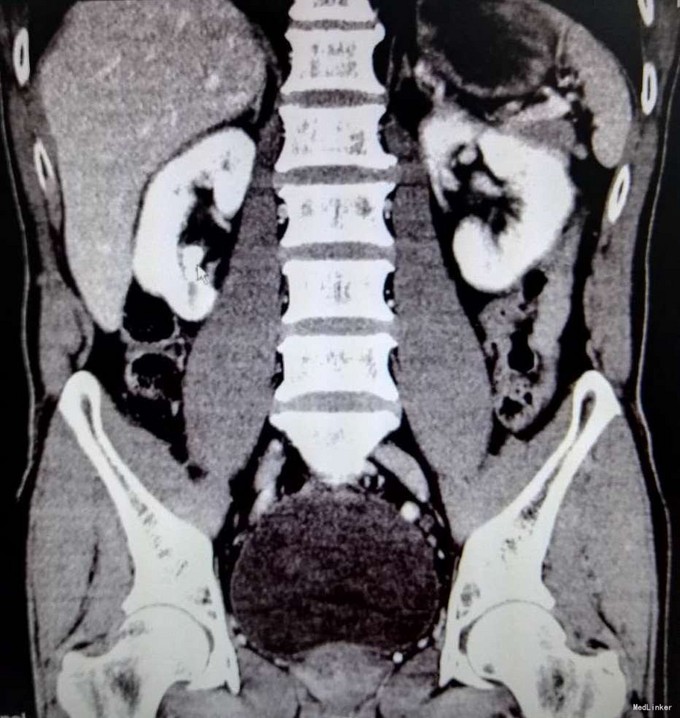

3、查体:右肾区叩击痛(+),右侧肋脊点、肋腰点压痛(+),余查体未见明显异常 4、辅助检查:我院KUB提示:右肾多发结石,CTU平扫+增强:1、右肾多发结石,右肾下极局限性萎缩2、双肾多发囊张,3、肝多发囊肿

5、肾结石(右肾多发结石) 6、住院后完善相关检查,双肾CTU平扫+增强如上述,诊断为右肾多发结石,行右侧输尿管逆行置管术,手术顺利,术后恢复较好,顺利出院